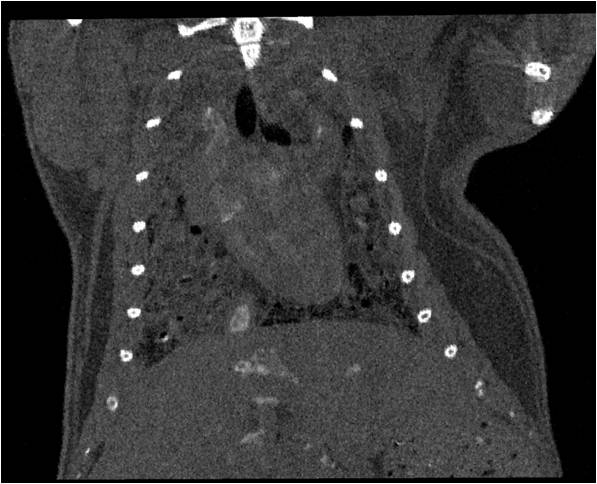

肺轉(zhuǎn)移

小鼠模式,22.5μm像素

正常

8天 14天

無造影劑注入 造影劑注入